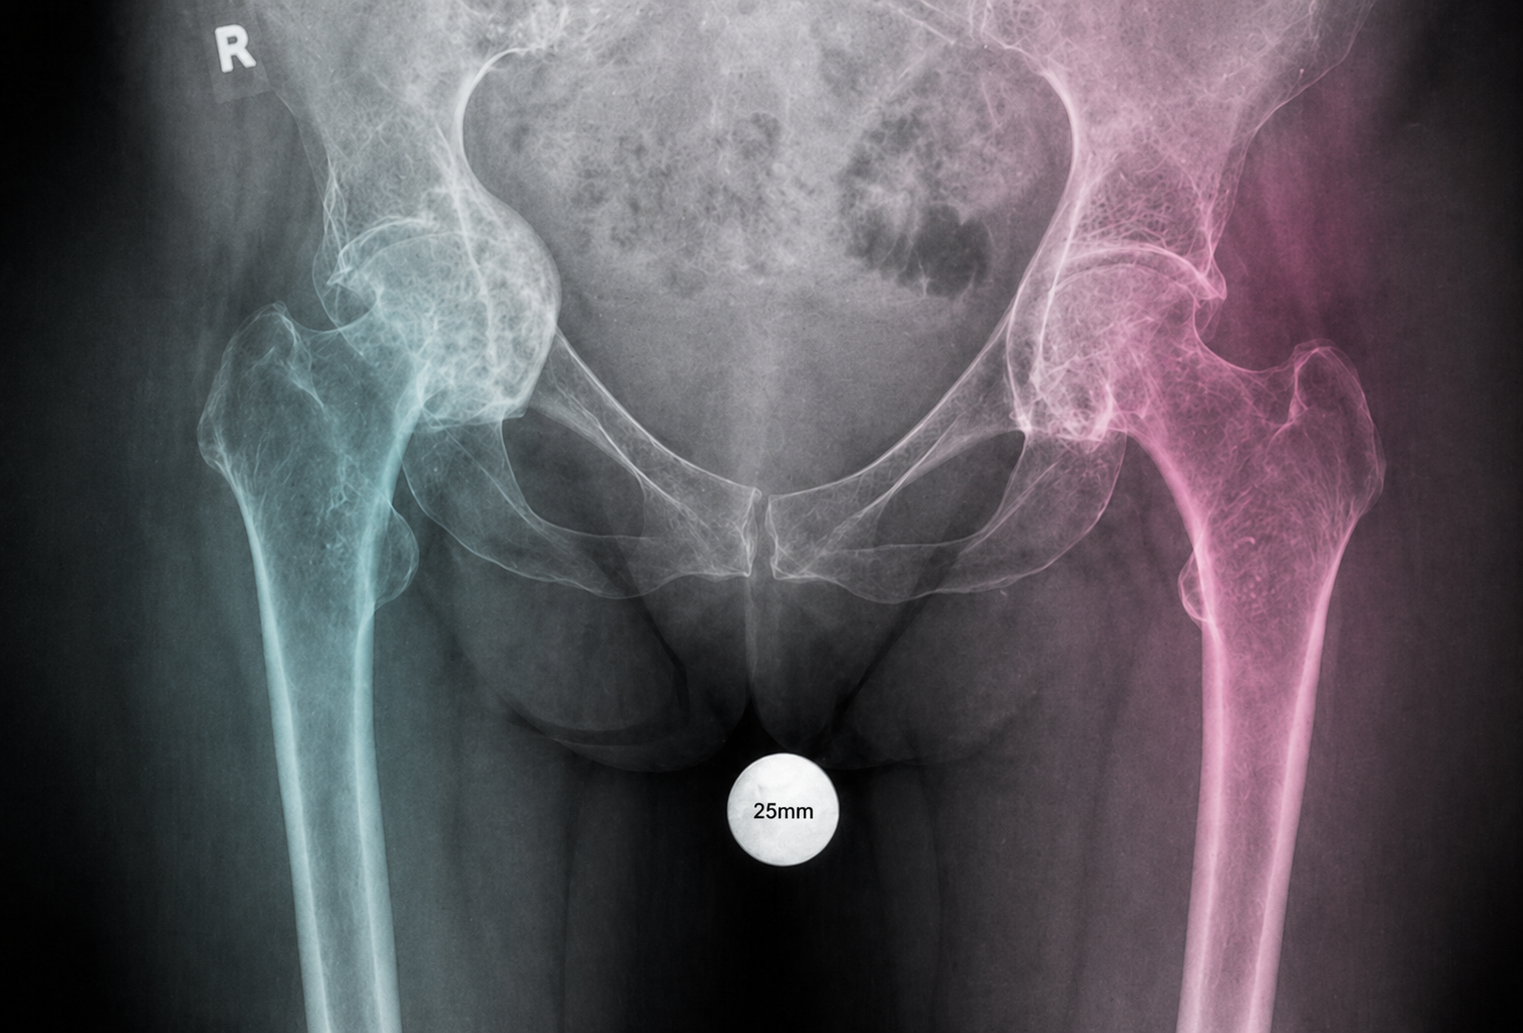

A compact guide for radiology teams on correct calibration sphere placement in orthopedic X-ray imaging. The marker must be positioned in the anatomical plane of the target joint so that digital scaling, measurements and preoperative templating remain clinically reliable.